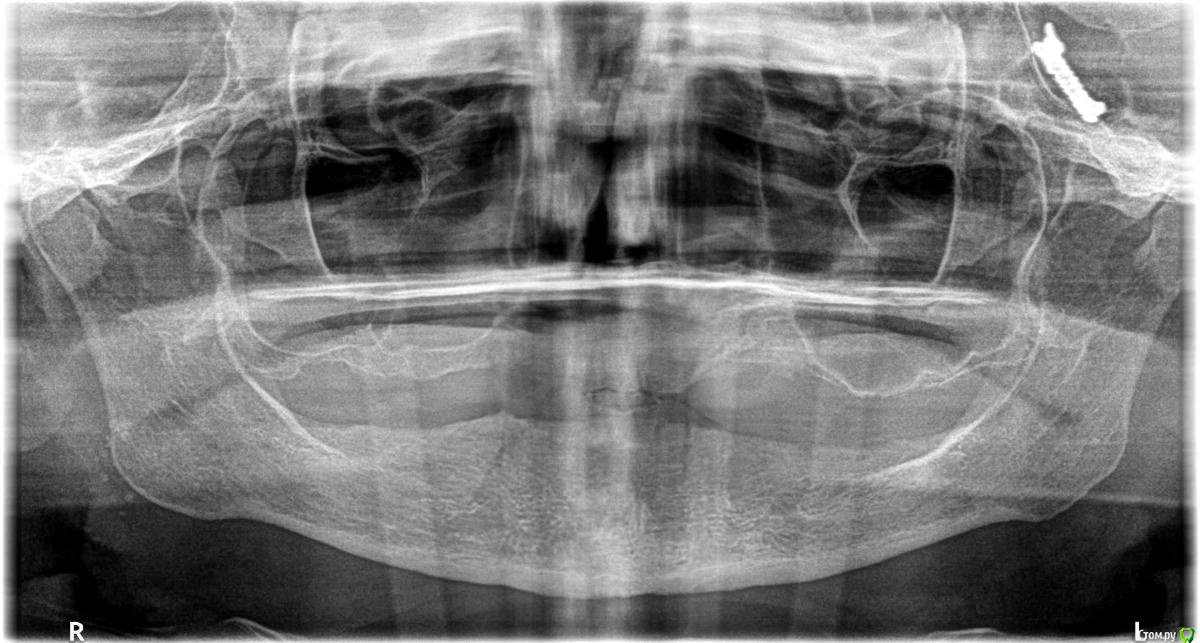

tigrosha86 Опубликовано 1 февраля, 2017 Поделиться Опубликовано 1 февраля, 2017 Здравствуйте!Моя мама длительно жалуется на дискомфорт в левой части лица, говорит что такое чувство что что-то мешает, есть не удобно.Неоднократно обращались в институт стоматологии, но там даже ни разу не направили на рентген.Короче, мне все это надоело, т.к. проблема есть - решения нет, а мама хочет себе протезы сделать, но сильно сомневается, что протезы исправят эту ситуацию. И я организовала ей в частной клинике панорамный рентген. Результат меня ошеломил, только я не знаю, что ЭТО. Смотреть слева - обозначена буквой L.Спасибо. Ссылка на комментарий

red_butler Опубликовано 1 февраля, 2017 Поделиться Опубликовано 1 февраля, 2017 Результат меня ошеломил, только я не знаю, что ЭТО похоже заколку с волос не сняли Ссылка на комментарий

tigrosha86 Опубликовано 1 февраля, 2017 Автор Поделиться Опубликовано 1 февраля, 2017 похоже заколку с волос не сняли Да нет, у мамы короткая стрижка.Это какой то инородный предмет Ссылка на комментарий

Большой Зеленый Опубликовано 1 февраля, 2017 Поделиться Опубликовано 1 февраля, 2017 Да, я серьезно. Вы не сталкивались с нашими докторами. Латвия, слышали про такое место на планете? Это заколка для волос "крокодильчик" .Удаляется путем нажимания на короткий рычажок.. 2 Ссылка на комментарий

tigrosha86 Опубликовано 1 февраля, 2017 Автор Поделиться Опубликовано 1 февраля, 2017 Это заколка для волос "крокодильчик" .Удаляется путем нажимания на короткий рычажок.. Я смотрю, здесь не врачи, а остряки...Повторяю: нету у мамы ни таких заколок, ни каких либо других. Ссылка на комментарий

red_butler Опубликовано 1 февраля, 2017 Поделиться Опубликовано 1 февраля, 2017 Я смотрю, здесь не врачи, а остряки...Повторяю: нету у мамы ни таких заколок, ни каких либо других. Сделайте новый снимок. Ссылка на комментарий

St. Опубликовано 1 февраля, 2017 Поделиться Опубликовано 1 февраля, 2017 Сделайте новый снимок.+1. Причем обязательно проверьте чтоб не было ничего металлического в области головы и шеи ( заколки, сережки, очки , цепочки, булавки и т.п.)И сравните оба снимка. Ссылка на комментарий